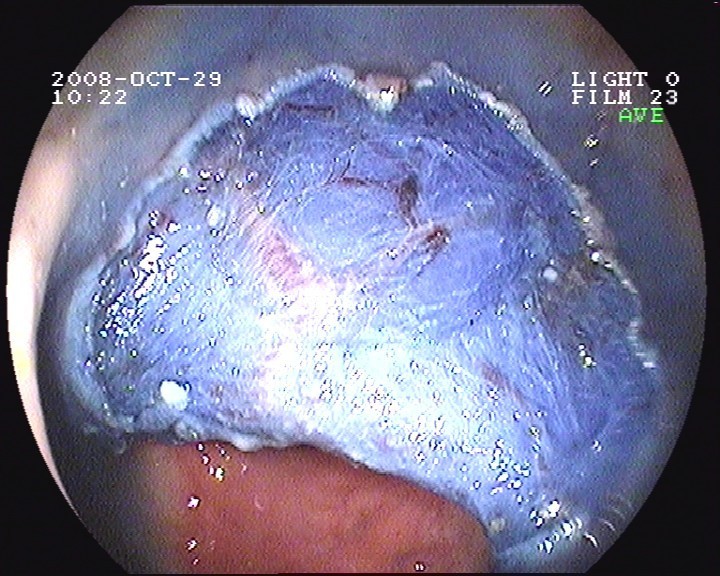

Coloskopie - riesiger rasenförmiger Polyp